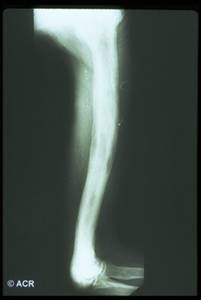

Il 30% della massa ossea viene persa prima che l'osteoporosi possa essere evidenziata dalle radiografie;

Evidenzia le fratture.

Reperti radiografici

Lisi ossea: riflette l'aumentata attività osteoclastica;

Sclerosi: riflette l'aumentata attività osteoblastica;

Aumento volumetrico dell'osso;

Lesioni litiche a "fiamma": riscontrabili a carico delle ossa lunghe;

Utile anche la scintigrafia ossea: può aiutare nel determinare l'estensione del coinvolgimento osseo, tuttavia non dovrebbe essere usata per porre diagnosi.